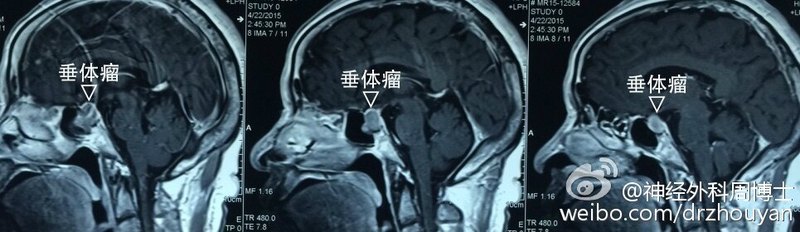

垂体瘤

治疗前患者以“头痛”为主要症状来院救治,CT提示囊实性病变位于鞍内,向上突入鞍上池,对垂体柄构成挤压,形成“垂体柄效应”导致泌乳素水平轻度上升,男性患者往往表现为性欲减退,性功能下降而不愿意诉说。治疗后治疗后5天患者病史较长,囊肿巨大,压迫鞍区硬膜导致疼痛为主的症状,予以常规经鼻中隔黏膜下入路后打开鞍底骨质,可见鞍底硬膜膨隆,压力极高,予以开放硬膜后可见囊液喷射性溢出,排空囊液后探查囊腔,可见正常垂体位于上方及两侧,予以硬膜修复缝合,鼻中隔黏膜还纳缝合后返回病房,鼻腔不填塞,较为舒适。术后复查核磁提示囊腔压力显著下降,垂体柄及垂体未见影响,5天后出院。